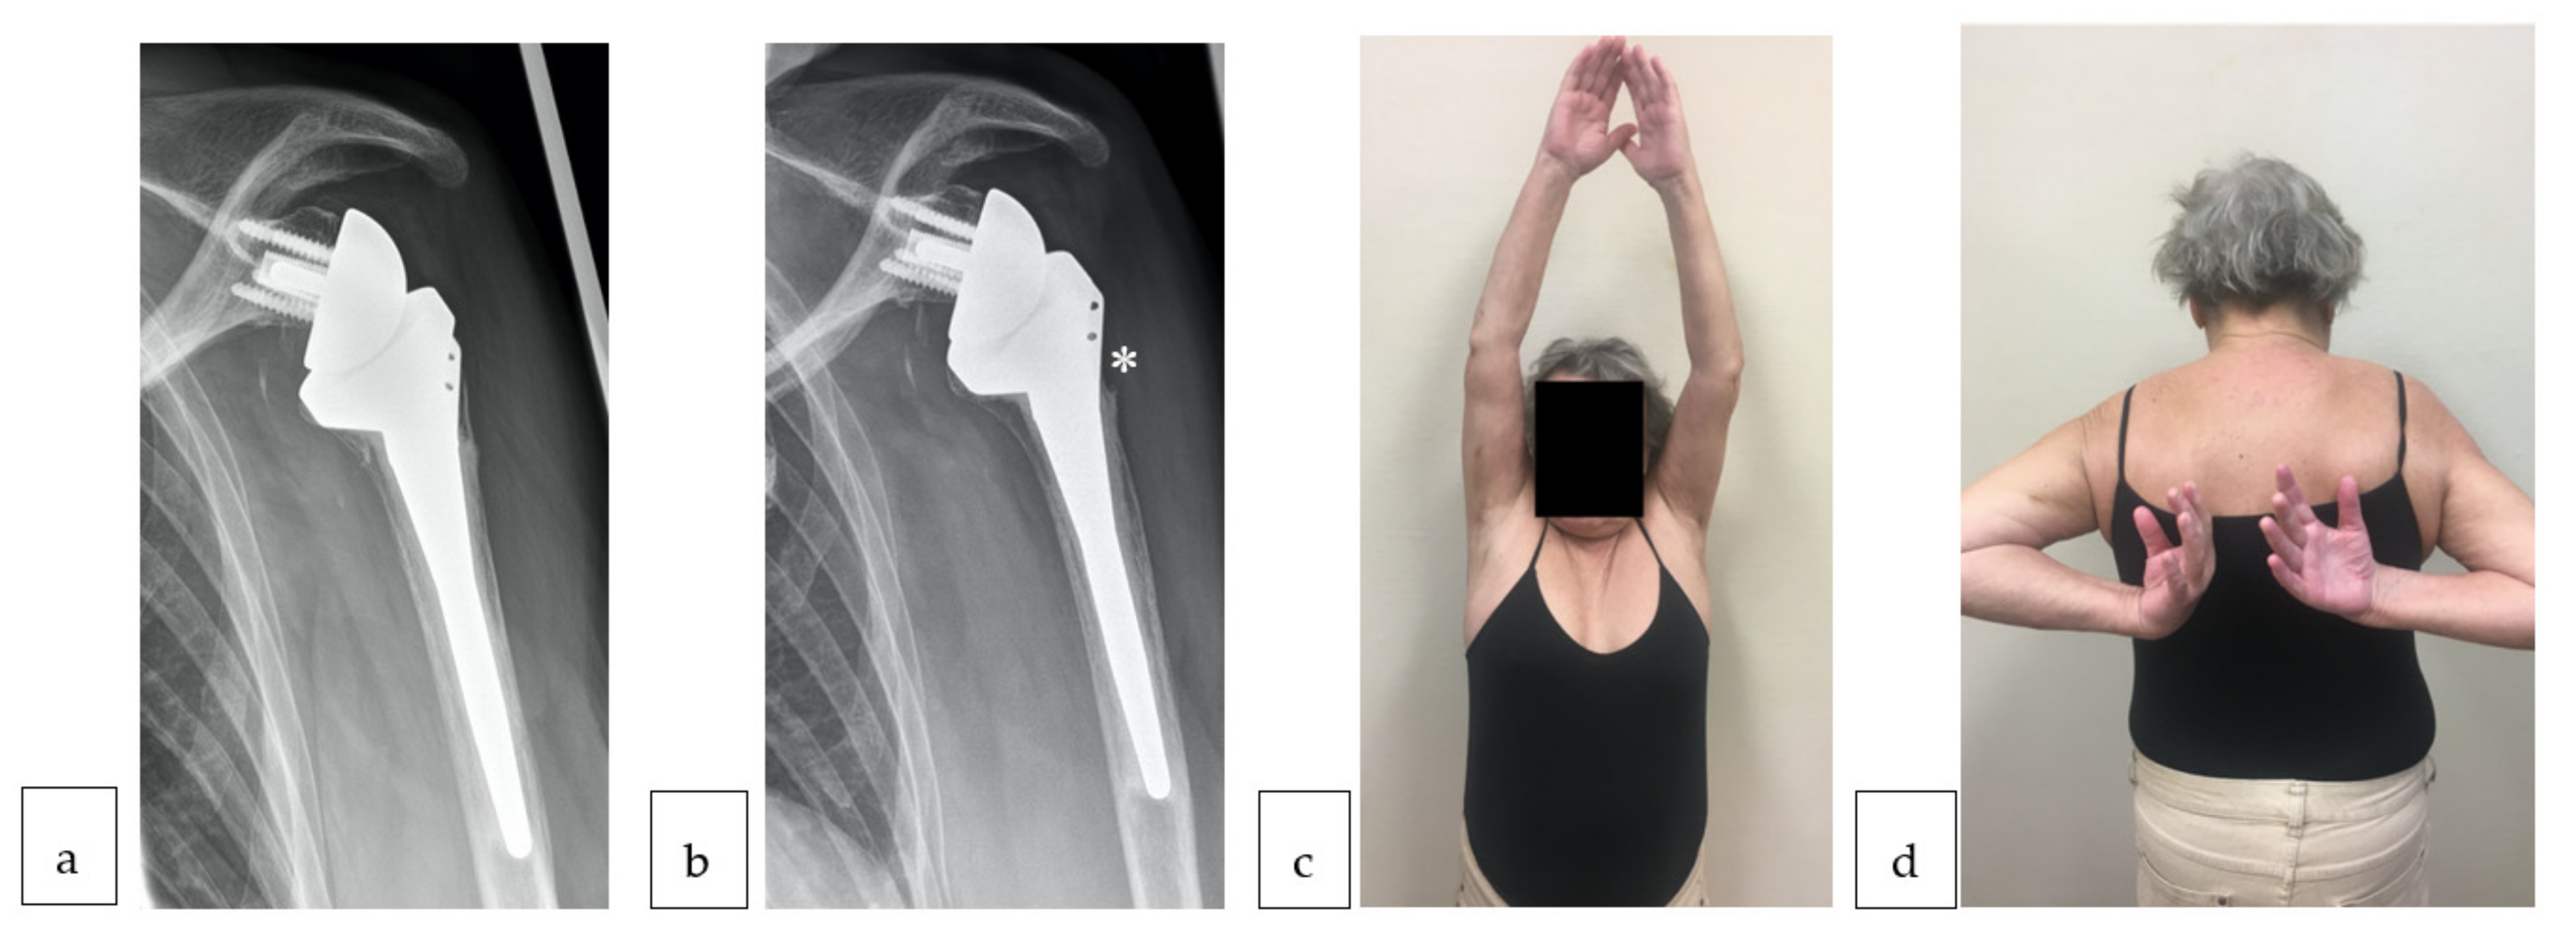

2.3. Clinical and Radiologic Evaluation

3.3. Clinical Impact of Tuberosity Healing and ERLS

3.4. Complication